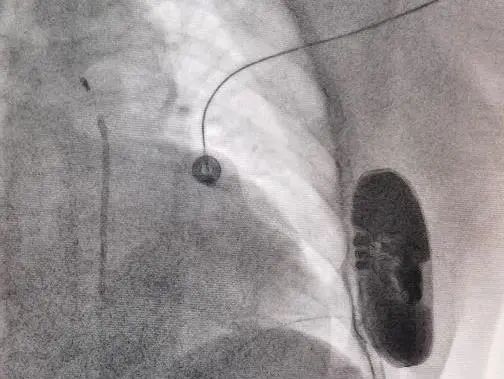

术后影像